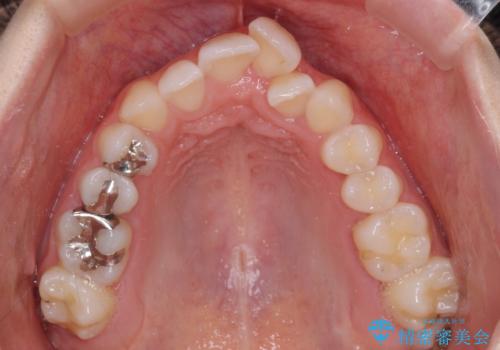

- 上下前歯のデコボコを気にして来院された患者様です。

上顎骨の横幅が狭く、奥歯は上顎よりも下顎が外側にある咬合状態でした。

歯列矯正では基本的に骨格を改善することはできませんが、急速拡大装置(MARPE)を使用することで上顎骨を側方に拡大させることができ、咬合状態を大きく改善することができます。

事前に急速拡大装置で側方拡大を行い、上下を目立たないワイヤー装置により歯列を整えていくこととしました。